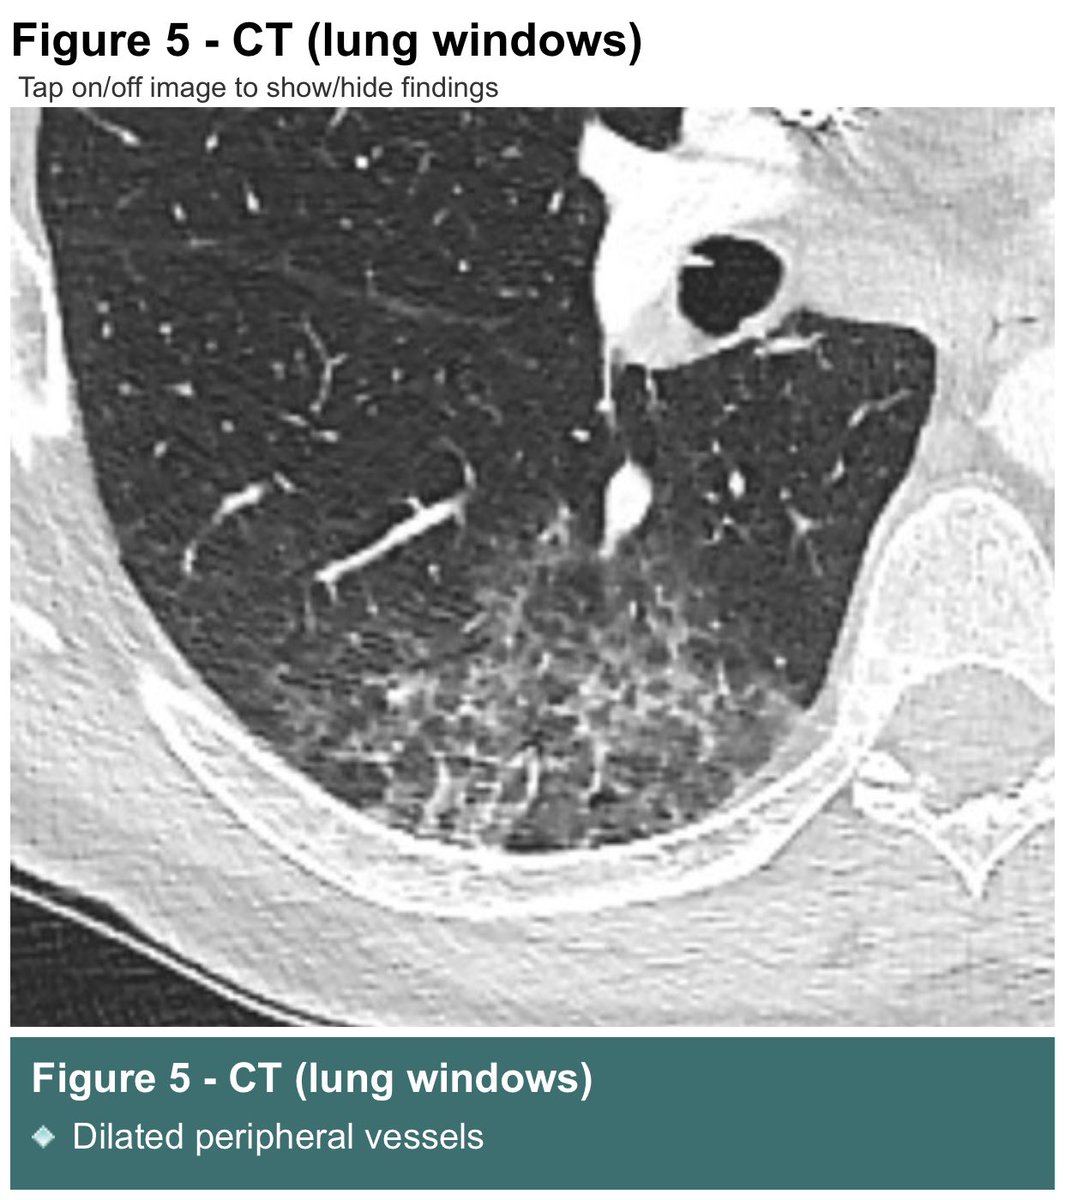

Dr Graham Lloyd-Jones Long COVID patients have abnormal 129Xe MRI RBC-to–alveolar tissue barrier ratios, which suggests abnormal oxygen and carbon dioxide gas exchange, for example due to pulmonary embolism or a thickening of the alveolar membrane. discovermednews.com/long-covid-pat…